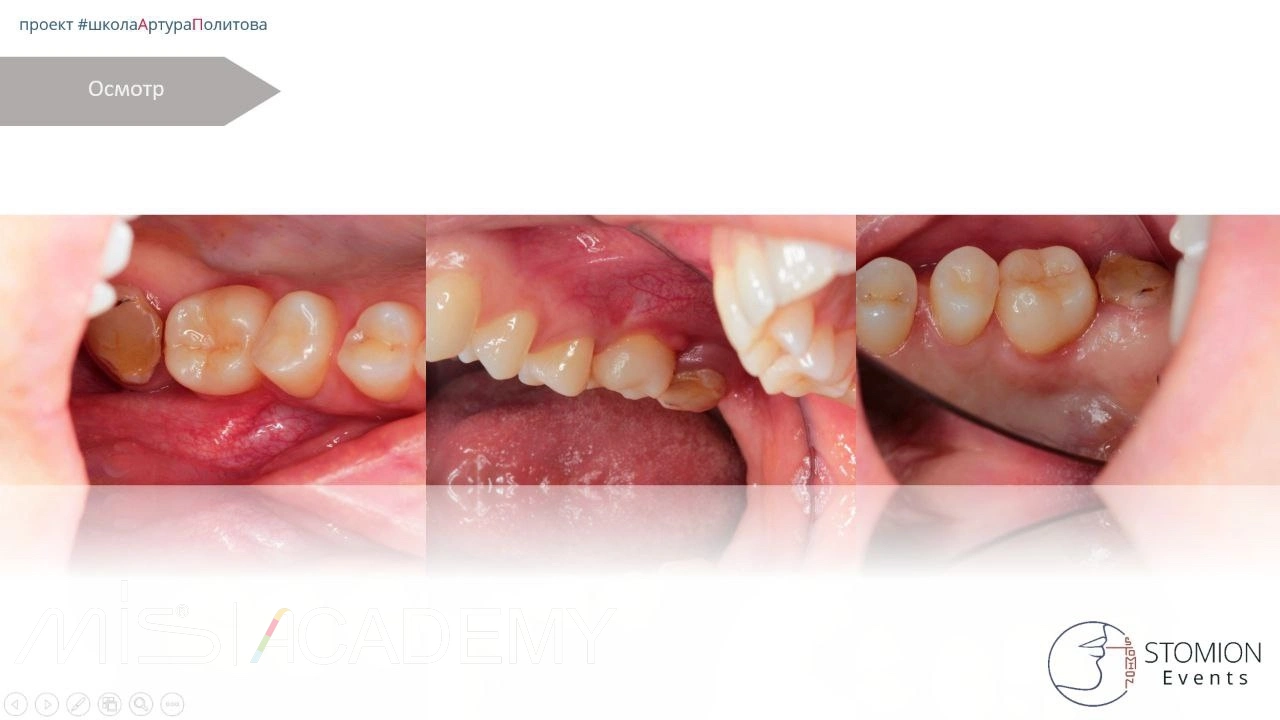

Пациентка: обратилась через месяц после удаления зуба 1.6.

Первичный приём в нашей клинике:

• Сняты швы.

• Проведена проба — отмечена миграция воздуха.

• Назначена асепта на постоянной основе 3 недели.

Контроль через 2 месяца:

• Свища нет.